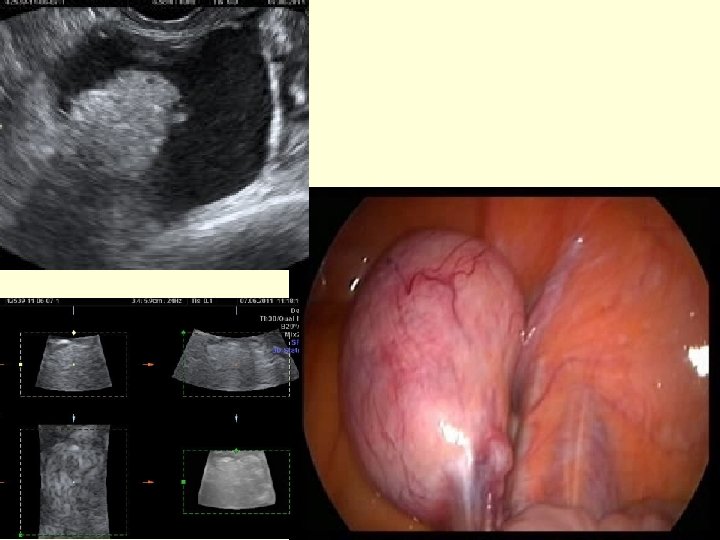

Cystadenomas

Endometrioma

Solid Mass

Dermoid cysts